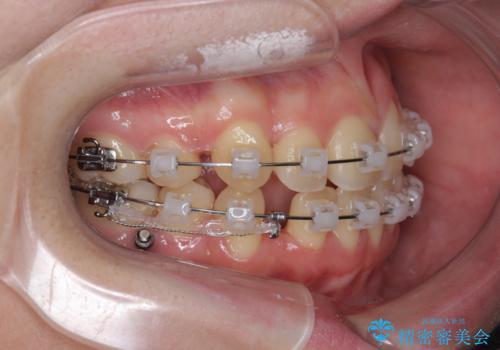

歯並びのせいで歯ブラシがしづらい マルチブラケットを用いた抜歯矯正

- 歯並びのがたつきにより歯ブラシがしづらく、今後虫歯になってしまう不安から、矯正治療を希望されて来院されました。

歯を並べるにはスペースが不足しているため、小臼歯の抜歯を4本行うマルチブラケット矯正による治療を計画します。

治療後は非常に歯ブラシがしやすくなったと、治療結果に満足いただくことができました。